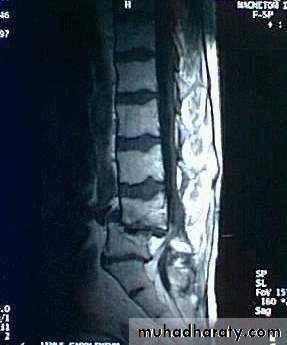

SPONDYLOLISTHESIS

Spondylolisthesis means forward translation of one segment of the spine upon another. The shift is nearly always between L4 and L5, or between L5 and the sacrum.Backward translation is called retrolisthesis.

Pathology:In the common lytic type, the pars interarticularis on both sides is disrupted (spondylolysis), leaving the posterior arch separated from the vertebral body anteriorly; the gap is occupied by fibrous tissue. With stress, spondylolisthesis developed.

The degree of slip is measured by the amount of overlap of adjacent vertebral bodies and is usually expressed as a percentage. With slipping there will be spinal stenosis.

X-ray:Lateral views show the forward shift of the vertebra above on the vertebra below.

The gap in the pars interarticularis is best seen in the oblique views.

CT-scan and MRI are helpful.